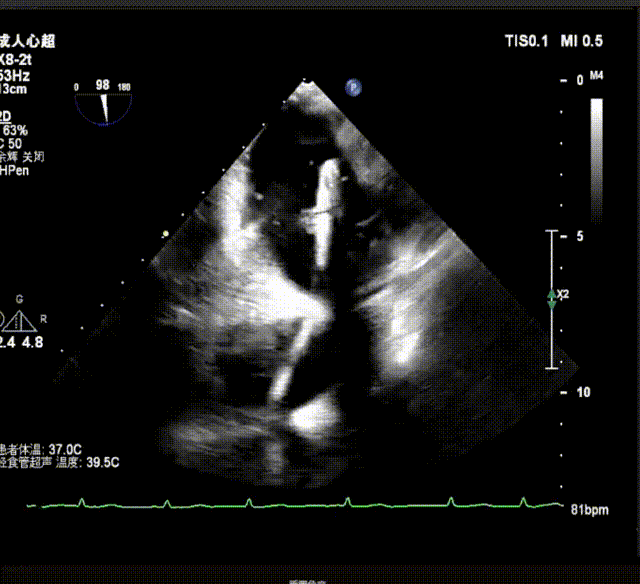

术前超声诊断

X-plane视窗可见二尖瓣2区脱垂;3D enface view示二尖瓣内P2脱垂,偏心性返流

反流束宽 15.4mm PISA半径 9mm,PISA 法估算EROA= 0.21cm²,Rvol=42ml

PW显示左肺静脉收缩期血流频谱呈逆向

3D模式测量二尖瓣瓣口面积5.57cm²;

二尖瓣口平均跨瓣压差=3 mmHg